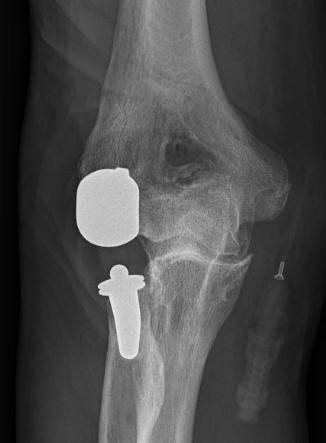

Coonrad-Morrey Discovery Elbow Latitude

Arthroplasty

4. Trial reduction

5. Insert cement restrictors / implant ulna and humeral prosthesis

6. Insert bone graft under anterior flange

7. Link components

8. Repair collaterals if needed